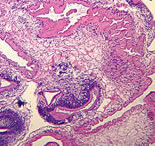

A 67-year-old woman visited her health care provider because of a subcutaneous

nodule located in the posterior area of her right shoulder. The

cyst was surgically removed. It measured three to four centimeters

in diameter and was filled with clear fluid. The material was submitted

for histological examination. Sections were made and stained with

H & E (hematoxylin and eosin). Figure A shows a large

area of the stained section captured using 50× magnification (5× objective)

from one slide, and Figures B and C show cropped areas using

200× magnification (20× objective). What is your diagnosis?

Based on what criteria?